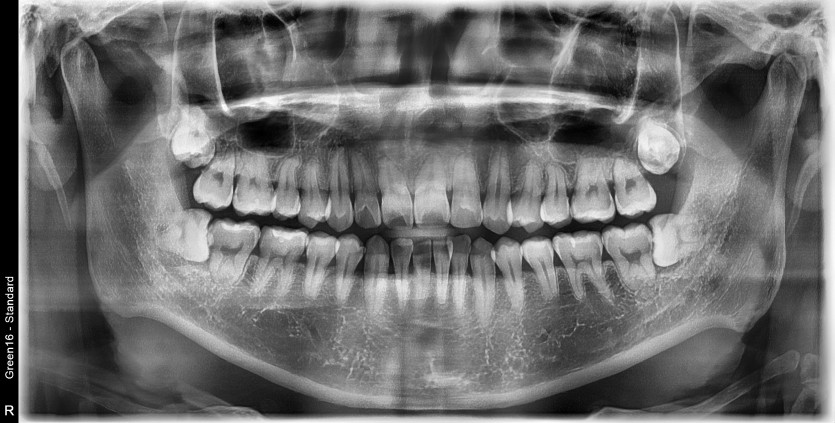

#38,48 사랑니 발치

구강 외과 전문의가 당일 발치했습니다.